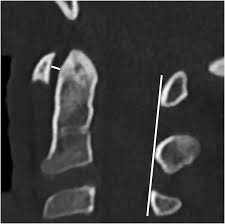

What should the width between the spinolaminar and posterior vertebral lines be in the cervicals vs.

What are lumbar puncture positions. Lower 1/2 of l4 or the l4/l5 ivd space. Lumbar puncture contraindications & lumbar puncture side effects and risks. Spinolaminar contour line connects the bases of the spinous processes. Trace the anterior, posterior and spinolaminar lines. Bone is expanded the cortex is thickened the trabeculae is coarse. The joint between the articular facets. Learn lumbar spine anatomy so that you can better understand your low back pain. What is the zygapophysial joint? Normally, a line (red arrow) drawn. Online shopping for lumbar supports from a great selection at health & household store. .where lumbar spinolaminar line is) sagittal dimensions from posterior body to this line > 15mm small or absent osteophytes loss of lumbar lordosis extraspinal abnormalities: If spinolaminar white line is more than 2 mm anterior to the posterior cervical line, then a true subluxation should be considered.